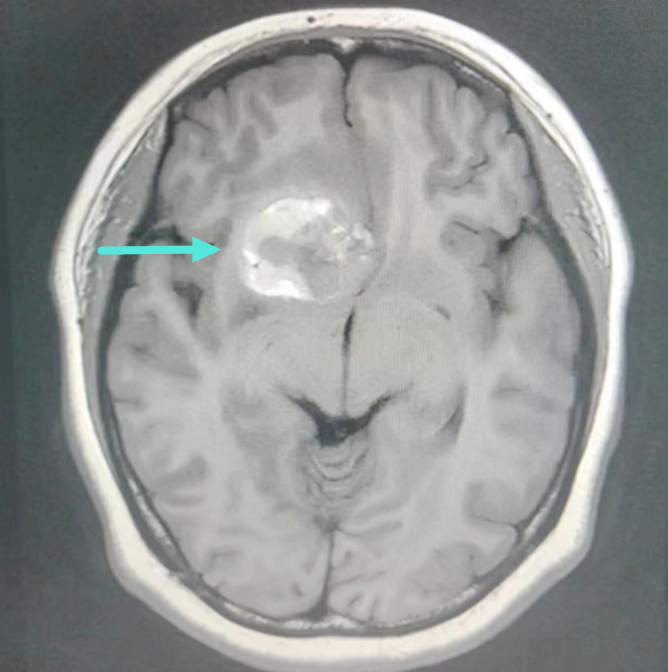

近日一女子因“反复头痛”症状到我院治疗,经详细检查后,发现右侧额叶深部血管瘤。神经外科学科带头人、副院长王鹏与神经外科二区负责人叶志其会诊后认为:患者诊断考虑为右侧额叶深部-基底节区海绵状血管畸形伴发育性静脉异常并出血,病灶体积大、结构复杂,已反复出血并导致头痛、呕吐等症状,如病情继续发展,将出现严重的颅高压症状,甚至有生命危险,神经外科团队迅速与患者家属沟通,为患者制定最佳治疗方案。

▲MRI提示右侧额叶深部-基底节区海绵状血管

畸形伴发育性静脉异常并出血